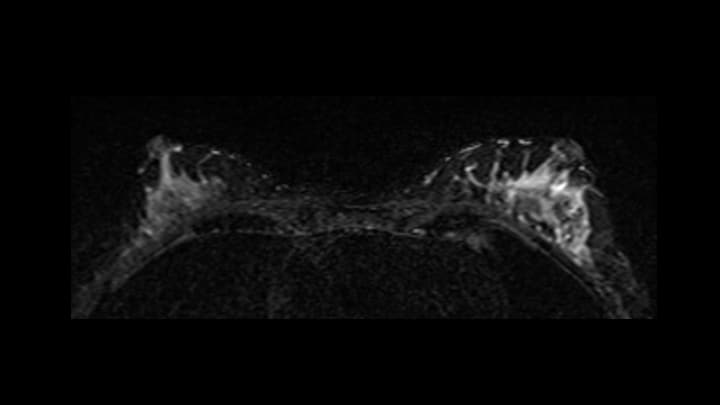

5. ダイナミックMRI 早期相

左乳頭外側にnon-mass enhancementを認める(矢印)